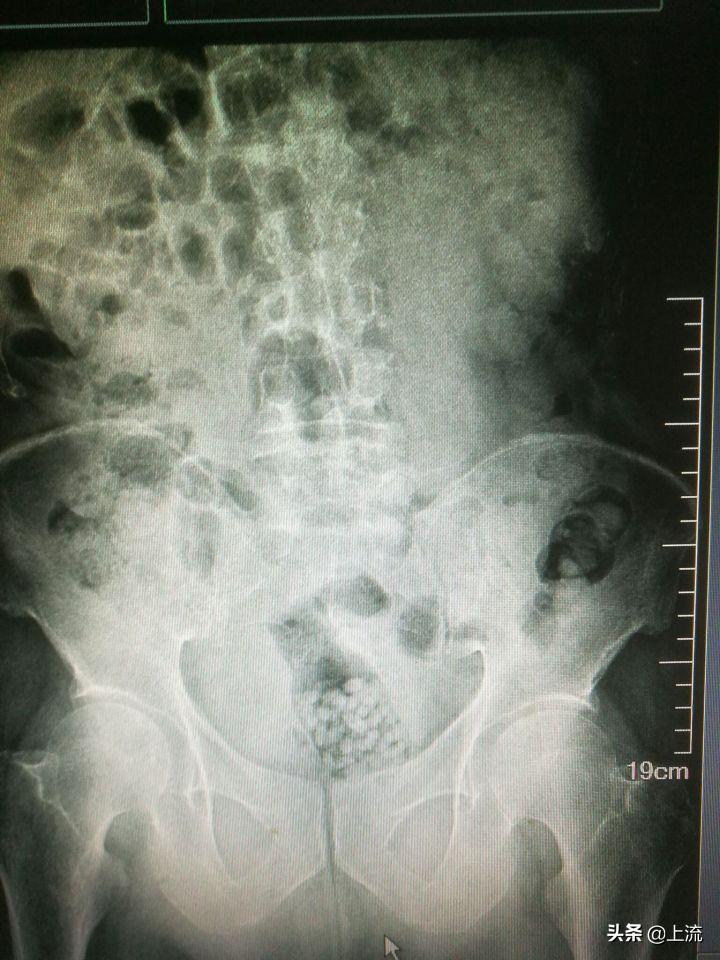

而面对这种直肠内有手机的优秀X光片,医生大概只能猜测,该病人可能是想测试这部诺基亚经典款卓越的超长待机、超频震动以及超强防水功能……对不起,编不下去了。

鉴于以上的人类迷惑行为,一名肛肠科医生见过了如此精彩纷呈的人体异物后,再看到什么都会见怪不怪了,于是这就考验着医生的另一项专业能力——编剧能力——如何能在不让病人家属知道真相的同时解释清楚这神奇的X光片。

△来源:医学手札